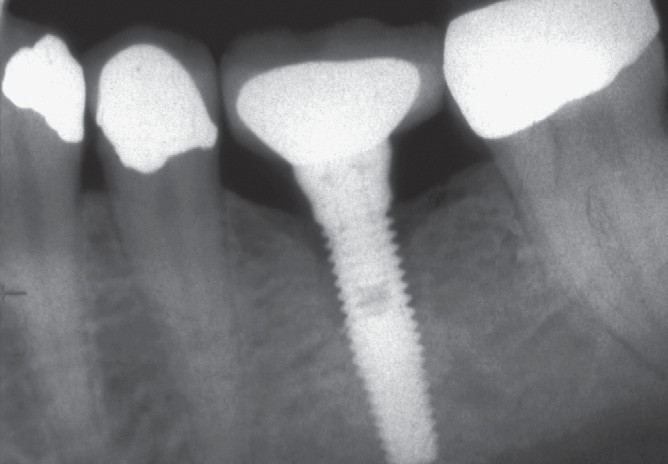

13. (Select ONE or MORE correct answer)

Which of the following is true regarding dental implant at site 2.6?